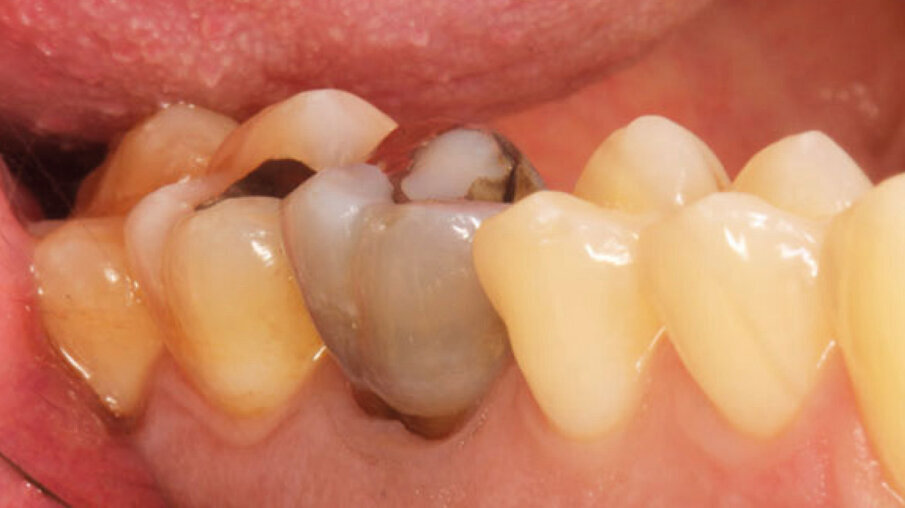

Un paziente maschio (ASA I), senza patologie croniche sistemiche e non fumatore, è stato sottoposto all’estrazione dell’elemento 16 a seguito del fallimento di terapie endodontiche e dell’impossibilità di eseguire un restauro coronale (Figg. 1a, 1b). Nella selezione del paziente sono stati criteri di esclusione: pregressa radioterapia nel distretto testa/collo, assunzione di farmaci che possano indurre ONJ, disordini ematici coagulativi, bruxismo, scarsa igiene orale domiciliare, occlusione instabile, carie non trattate, malattia parodontale non controllata, denti adiacenti a quelli da estrarre con mobilità di grado I o superiore, aspettative di risultato irreali, impossibilità o non propensi a tornare ai controlli di routine e di follow-up. La situazione dei tessuti è stata valutata pre-operatoriamente tramite radiografia periapicala (Fig. 1c) (VistaScan Mini Plus, Dürr Dental). Tramite la CBCT pre-operatoria è stato possibile fare una programmazione implantare. Sulla base dell’anatomia coronale è stata definita la posizione implantare (OnDemand3D, Cybermed), da questa analisi sono stati decisi anche il diametro e la lunghezza dell’impianto.

Fig. 1a - Foto iniziale occlusale.

Fig. 1b - Foto iniziale vestibolare.